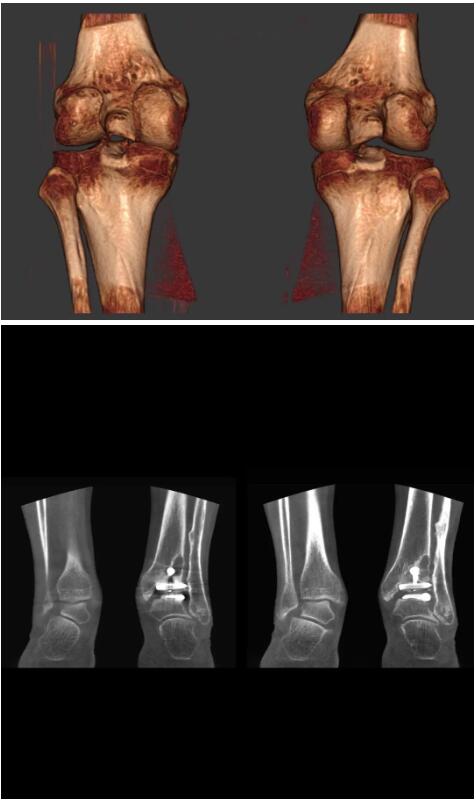

以下是這些“特立獨(dú)行”的CT所拍出來(lái)的圖像: